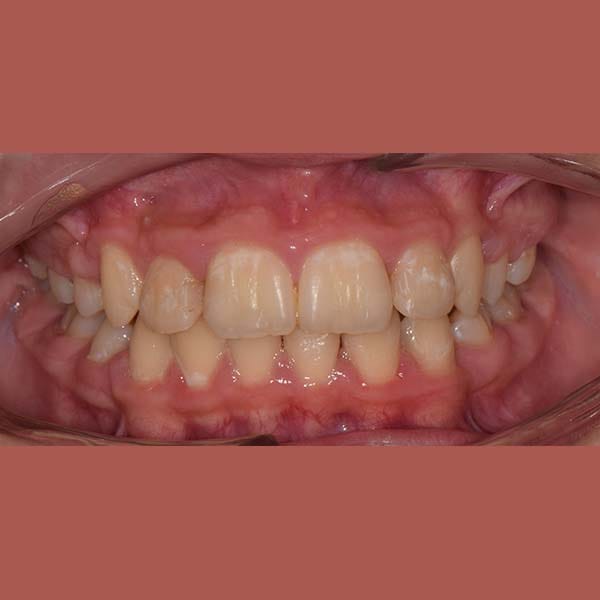

BEFORE